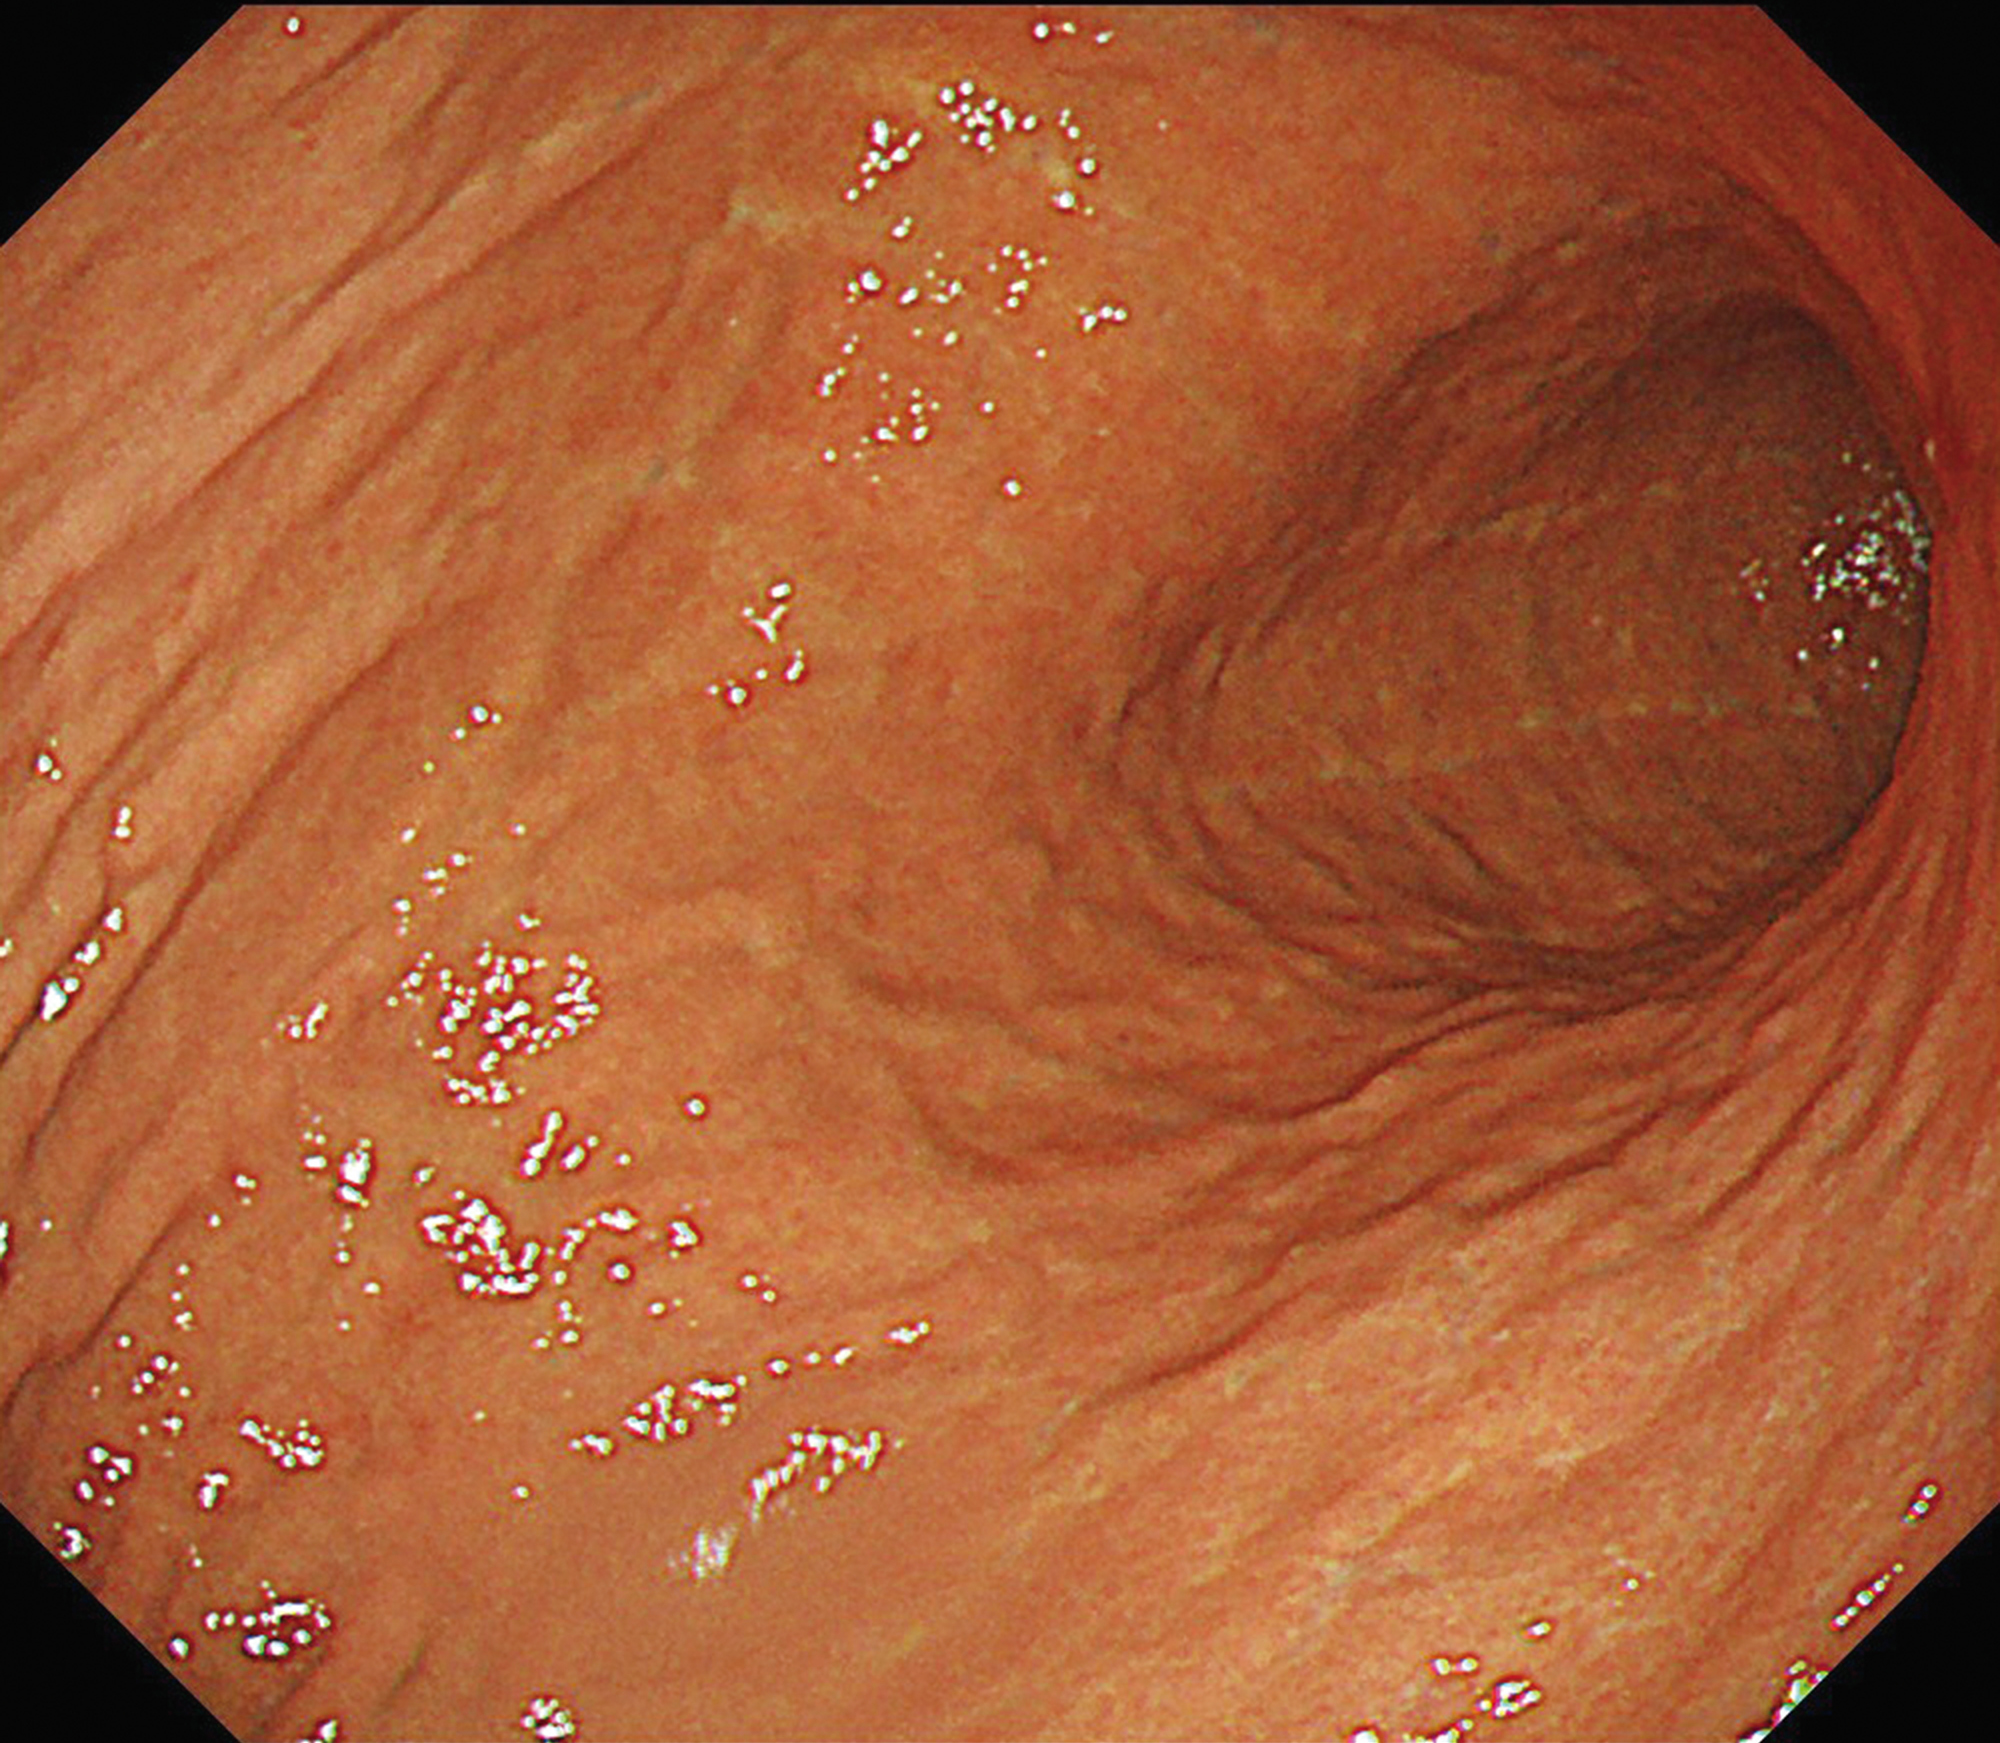

EVIS X1×GIF-1200N 症例画像

胃体部 見下ろし観察

1視野で体上部から胃角まで明るい視野での観察に貢献する